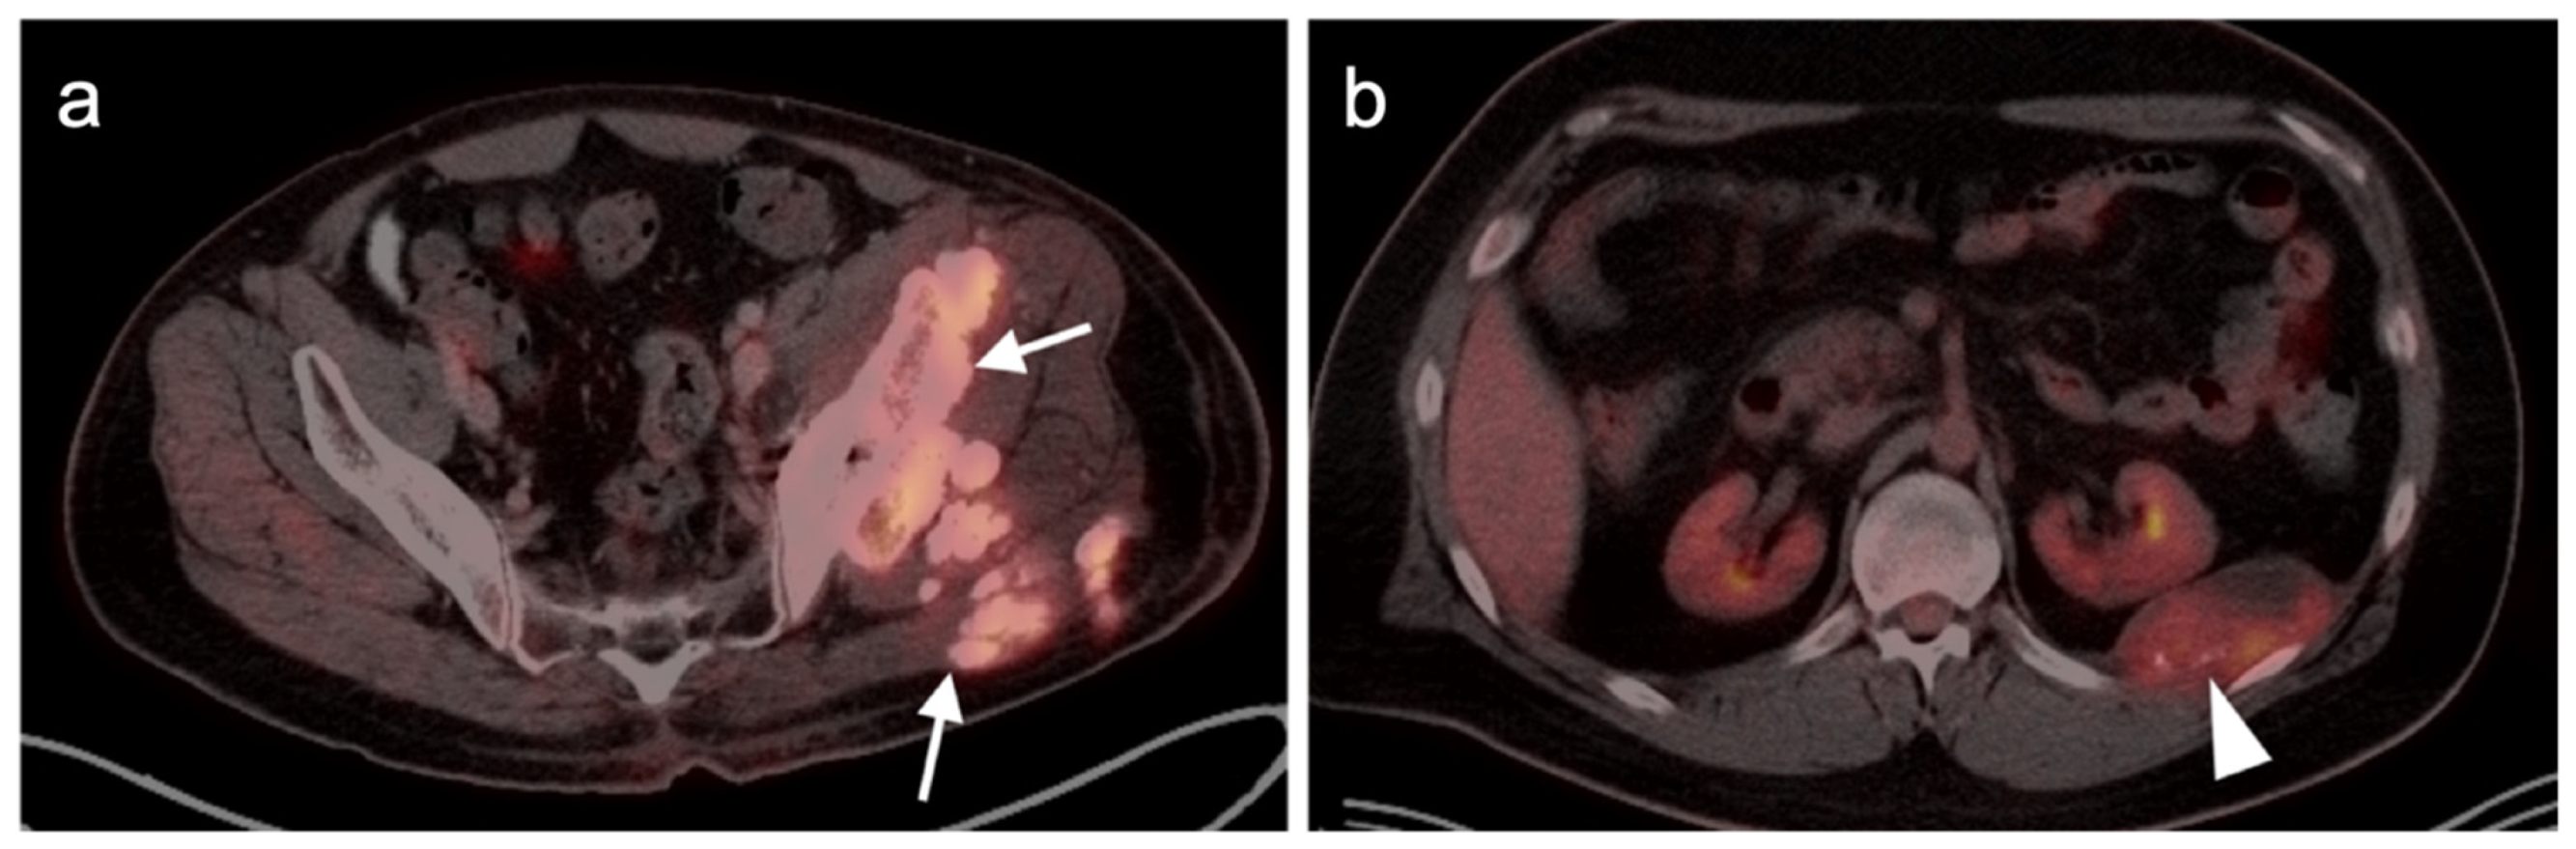

4. Neuroendocrine Tumors

4.1. Epidemiology and Agents

4.4. Bronchial Carcinoid

4.5. Pheochromocytoma and Paraganglioma